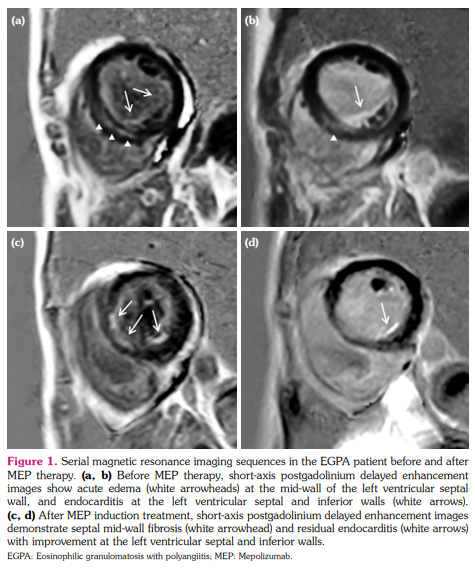

A 36-year-old female presented to our hospital with dyspnea and palpitation that had lasted for one month. Based on bronchial asthma, mononeuritis multiplex, and blood eosinophilia with extravascular infiltration,[6] the patient had received an EGPA diagnosis a year ago. She was in remission under combined CYC/GC induction therapy. At admission, laboratory tests revealed positive antimyeloperoxidase and increased levels of eosinophils (7,140/µL) and cardiac biomarkers. Echocardiography and magnetic resonance imaging demonstrated impaired left ventricular ejection fraction, myocardial edema, and diffuse mid-wall and endocardial enhancement, indicating endomyocarditis with cardiac insufficiency (Figure 1a, b). Holter monitoring revealed paroxysmal atrial tachycardia and atrial/ ventricular premature contractions. Glucocorticoid and cardiac supporting agents were prescribed for the disease relapse with heart involvement. The patient refused CYC induction therapy due to the side effects from earlier exposure. There was a more than 90% decrease in blood eosinophilia with stationary follow-up counts less than 150/µL following subcutaneous injection of 100 mg MEP quadriweekly (i.e. one time every four weeks). Twelve months after therapy, in addition to absent clinical symptoms and normalized biomarker levels, cardiac examinations showed normalized rhythm and left ventricular ejection fraction, resolved myocardial edema, and reduced mid-wall and endocardial delayed gadolinium enhancement (Figure 1c, d). No adverse effects were observed. The patient had a complete remission with sparing daily use of GCs.